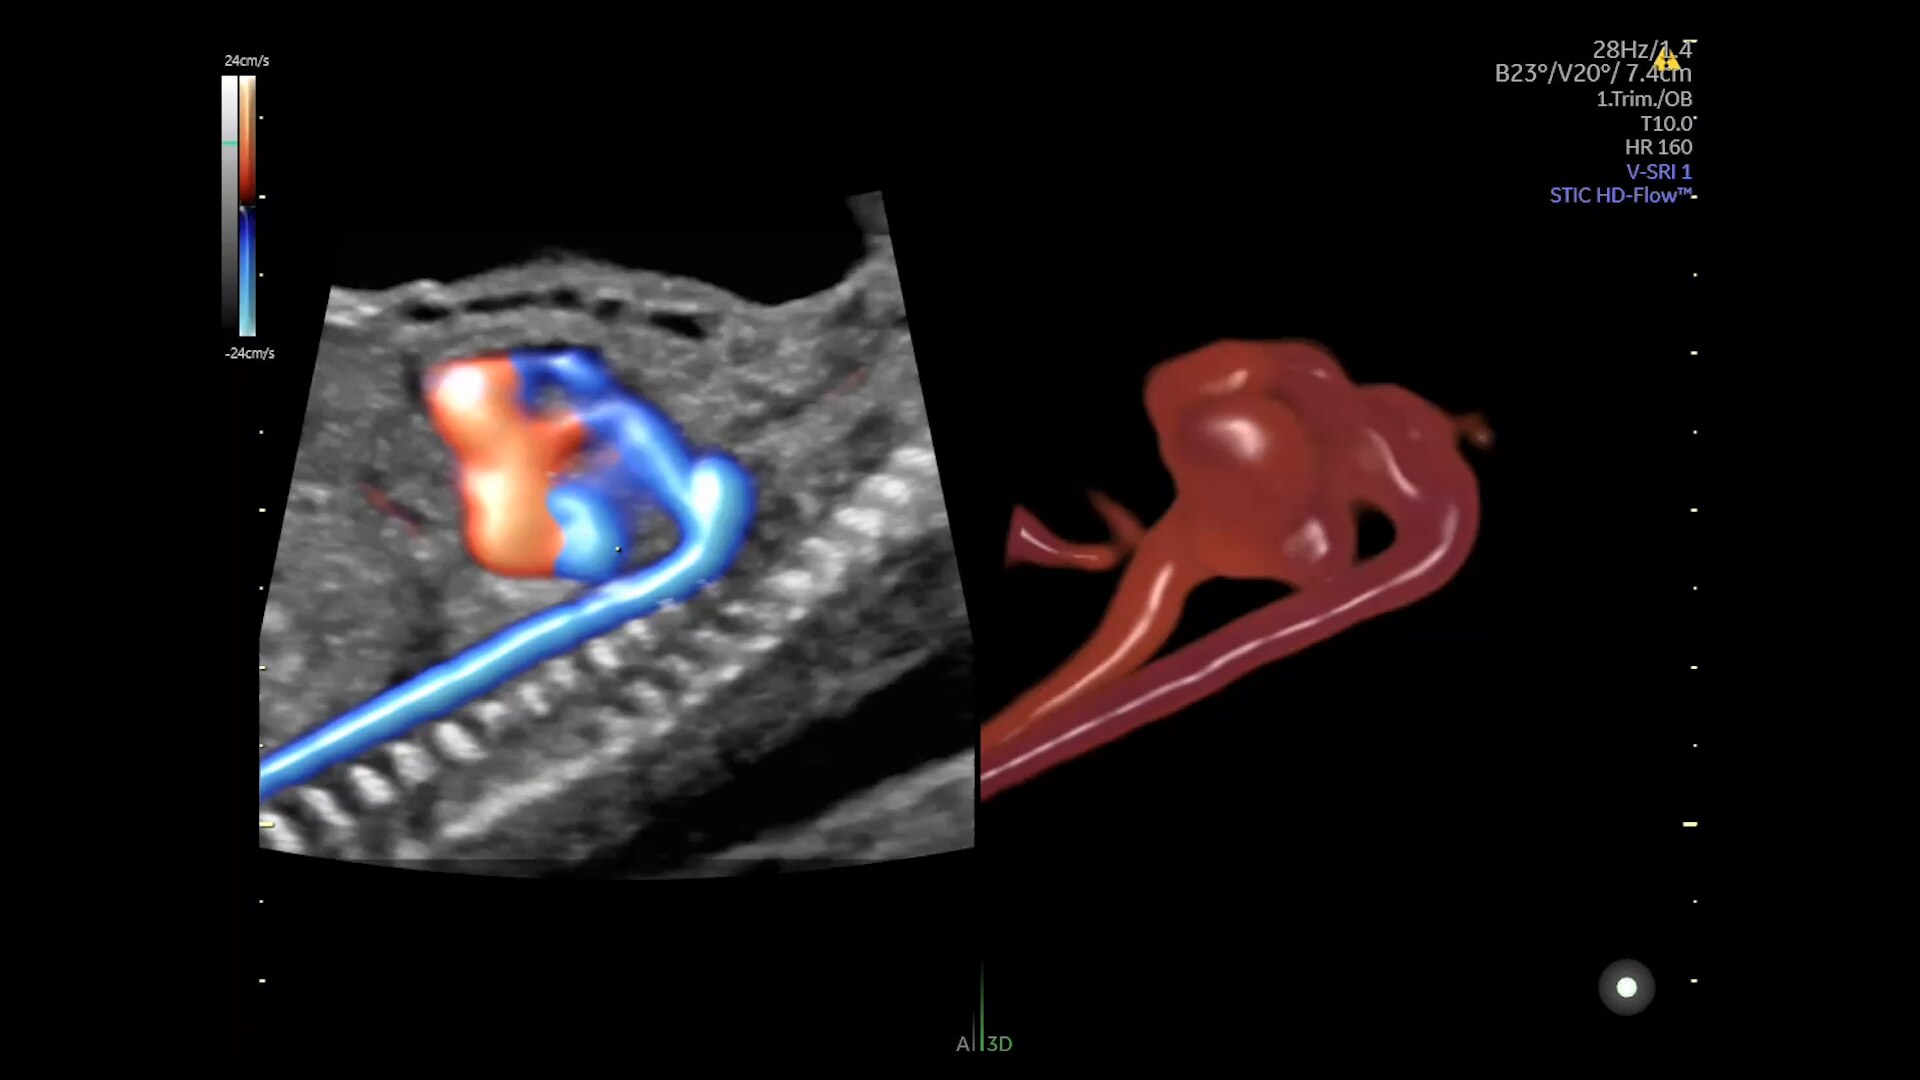

Voluson is pushing imaging boundaries to make blood flow assessment faster and easier. Our advanced technologies, including Graphic flow, Radiantflow, Slowflow, and Radiant imaging, increase resolution and sensitivity in color and pulsed wave Doppler for unprecedented clarity

Hemodynamic Visualization

Provides a graphical representation of the trajectories of the blood cells in real-time to visualize complex blood flow quickly and clearly, helping you to differentiate normal from abnormal hemodynamics